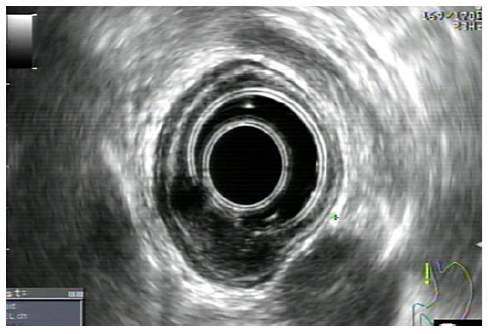

One week before the scheduled endoscopy, the patient once again presented at the ED, experiencing a recurrence of melena for 2 days and a blood count showing a hemoglobin of 11.6 g/dL. Subsequent endoscopy unveiled a distinctive 15 mm nodular subepithelial lesion at the gastroesophageal junction, with ulceration and a visible vessel at the proximal margin of the gastric mucosa. It was treated with 4 mL of diluted adrenaline injection and a clip placement on the vessel (shown in Fig. 2). An endoscopic ultrasound (EUS) revealed a homogeneous and hypoechoic lesion measuring 15 × 6 mm with well-defined limits at the deep mucosa (shown in Fig. 3). No local suspicious lymph nodes were observed. Histological examination of the biopsies of the lesion confirmed the presence of an adenocarcinoma. Subsequent computed tomography scans of the chest and abdomen revealed that the lesion retained clear cleavage plans with the surrounding structures, without suspicious adenopathies in its vicinity. After staging, the patient decided to change the health institution, which led to a month-long delay in treatment. Following a comprehensive multidisciplinary discussion, it was decided to proceed with a surgical approach, namely a distal esophagectomy and total gastrectomy.

Fig. 3 Homogeneous and hypoechoic lesion of 15 × 6 mm and well-defined limits, originated at the deep mucosa without local adenopathy’s.